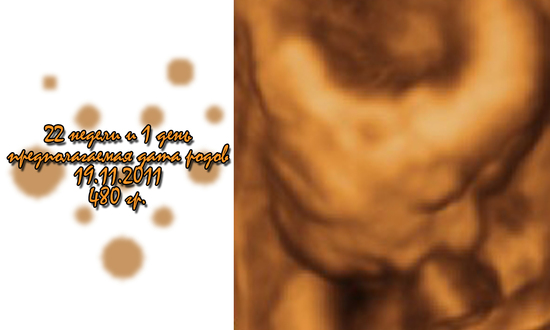

Наш сынок :)

вот наше чудо. 22 недели и 1 день... очень резвый малыш, всё никак не давал измериться, пинался и руками и ногами.так напинался, что в конце пошёл тонус :( ритка, как всегда, пищала, считала пальчики.смотрела что он мальчик :))))))))) гладила его и смотрела реакцию.короче счастья у нас полные штаны. в целом всё хорошо, чуть увеличены лоханки, но меньше, чем в прошлый раз...а у меня почка увеличена :( зато он растёт и буянит-это главное..наш шилопопик :))))